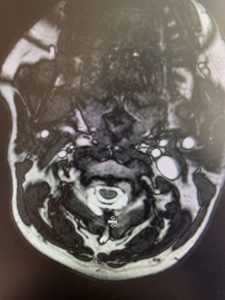

(2a) Lateral Flexion cervical x-rays demonstrating 8mm of splaying of the C34 interspinous distance

(2b) Lateral Flexion cervical x-rays extension image demonstrating 8mm of splaying of the C34 interspinous distance.

The fluid was possibly consistent with CSF versus chronic hematoma. The patient was also noted to have a high signal within the interspinous space of C3-C4. This high signal was consistent with a ruptured C3-4 interspinous ligament. Cervical flexion-extension x-rays demonstrated 6 mm of widening of the C3-4 interspinous space on flexion x-ray consistent with cervical instability (Fig. 2a and 2b).